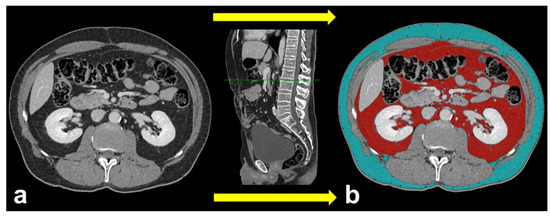

This cross-sectional observational study shows a significant decrease of SAT in ccRCCp patients compared to ccRCCa patients (Figure 3 and Figure 4).

Figure 4.

Axial CT images showing the orange ROIs of SAT areas in ccRCCa patients (a–c) and ccRCCp patients (d–f), the tumors in ccRCCa patients (yellow arrows in a–c) and ccRCCp patients (yellow arrows in d–f) and peritumoral collateral vessels in ccRCCp patients (red arrows in d–f). Note that there is a clear reduction of SAT in ccRCCp patients (d–f).